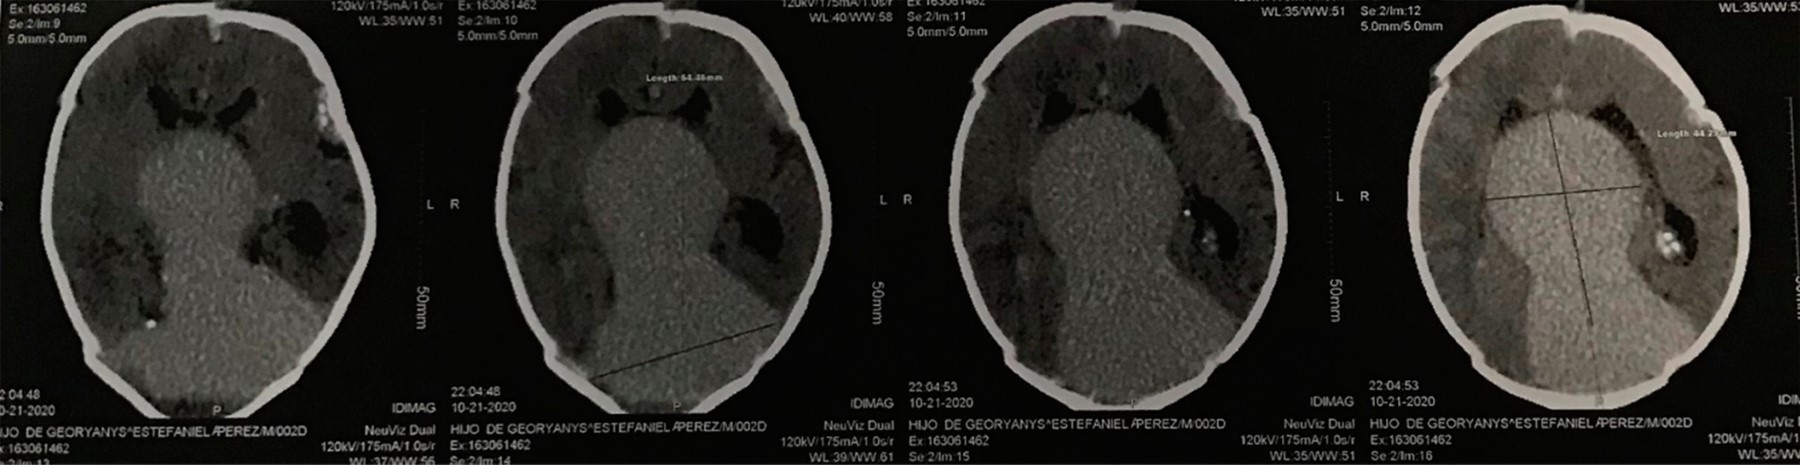

A los dos meses fue llevado al hospital por intolerancia a la vía oral. Se solicitó tomografía cerebral, documentando hemorragia intraventricular. Se detectó anemia grave e ingresa a Unidad Cuidados Intensivos (UCI). Se realizó nueva angiorresonancia cerebral, evidenciando aneurisma gigante de la vena de Galeno, hidrocefalia obstructiva y trombosis del seno longitudinal superior. Quince días después se realizó panangiografía cerebral con embolización de fístula de la vena de Galeno, sin complicaciones. Por la hidrocefalia, se llevó a cabo derivación ventrículo-peritoneal. Se egresó al estar estable.

Cinco meses después de internamiento anterior, el paciente es llevado al servicio de Urgencias con signos de hipertensión endocraneana, por lo cual se ingresó a la UCI. En imagen de tomografía cerebral se identificó hemorragia intracraneana masiva (Figura 4), lamentablemente el paciente se deterioró progresivamente llegando a muerte cerebral y fallecer.

Figura 4